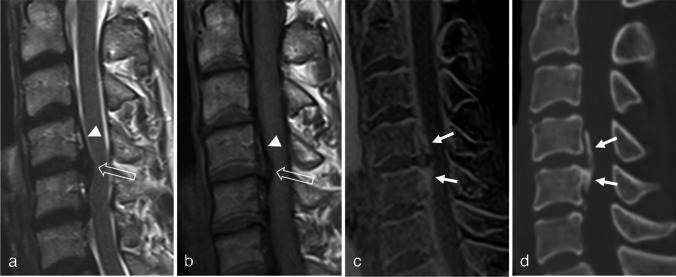

目的:比较三维快速低角度镜头(FLASH)与常规MRI序列对OPLL的诊断价值。材料和方法:本回顾性研究包括106例颈椎MRI和CT检查。OPLL组和对照组分别入组39例和67例患者。比较常规MRI使用涡轮自旋回波(TSE)和常规MRI加3D FLASH检测OPLL的诊断性能和读取器置信度。还计算了观察员间的一致意见。根据检测OPLL所需的序列,在OPLL组中定义了三个亚组(TSE组:仅通过检查TSE诊断为OPLL的病例;3D FLASH组:同时通过TSE和3D FLASH进行诊断的病例;无组:未经MRI诊断的病例)。比较各亚组间上pll的厚度。结果:常规MRI加入3D FLASH后,两种读卡器的诊断性能均有提高,其中读卡器2的差异有统计学意义(p = 0.006)。结论:3D FLASH与常规T1、t2加权成像相结合可有效检测OPLL。

Materials and methods: This retrospective study included 106 patients who underwent cervical spine MRI and CT. Thirty-nine and 67 patients were enrolled in the OPLL and control groups, respectively. Diagnostic performance and reader confidence for detecting OPLL were compared between conventional MRI using turbo spin echo (TSE) and conventional MRI plus 3D FLASH. Interobserver agreement was also calculated. Three subgroups were defined within the OPLL group according to the sequences required for detecting OPLL (TSE group: cases that were diagnosed as OPLL by reviewing only TSE; 3D FLASH group: cases that were diagnosed by reviewing both TSE and 3D FLASH; none group: cases that were not diagnosed on MRI). The thickness of the OPLL was compared between the subgroups.

Results: The diagnostic performance of both readers improved when 3D FLASH was added to conventional MRI, and the difference was statistically significant for reader 2 (p = 0.006). After adding 3D FLASH, reader confidence significantly increased (p < 0.001), and interobserver agreement improved from good to excellent. The three subgroups exhibited significantly different OPLL thicknesses (p = 0.008), with the thickest in the TSE group (4.5 mm), followed by the 3D FLASH (3.4 mm) and None groups (2.4 mm).

Conclusion: 3D FLASH can be helpful for detecting OPLL when combined with conventional T1- and T2-weighted imaging.